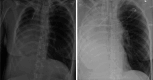

Postpneumonectomy syndrome (PPS) is a rare complication after pneumonectomy characterised by severe mediastinal shift leading to airway compression and respiratory distress. We present a case of a woman in her mid-40s who developed PPS following a right pneumonectomy for bronchial mucoepidermoid carcinoma. Surgical treatment of PPS had not previously been performed in Denmark by Danish surgeons, which is why we consulted with a British surgeon. The surgery was performed in Denmark.The procedure resulted in immediate respiratory improvement, and the patient was discharged 22 days postoperatively. Follow-up demonstrated sustained airway patency and no signs of cancer recurrence. This case highlights the feasibility and effectiveness of surgical management of PPS in centres with limited prior experience and supports mediastinal repositioning with prosthetic implants as a viable treatment option in severe cases.